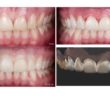

LE POINT DE CONTACT EN PROTHÈSE UN POINT CLÉ POUR L’ESTHÉTIQUE ET LA FONCTION

POINT DE CONTACT INTERPROXIMAL EN ZONE ESTHÉTIQUE POINT DE CONTACT INTERPROXIMAL ET ESTHÉTIQUE GINGIVALE EN SECTEUR ANTÉRIEUR L’esthétique gingivale en…

ET SI L A PHOTO DEVENAIT NOTRE MEILLEUR OUTIL CLINIQUE ?

INTRODUCTION : PHOTOGRAPHIER, UN ACTE CLINIQUE À PART ENTIÈRE La photographie a longtemps été perçue comme une activité annexe à…